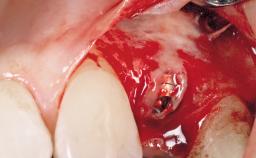

Late Flapless Placement of an Implant in a Maxillary Left Central Incisor Site

A 39-year-old male patient presented with a chief complaint of discomfort and gingival discoloration around his maxillary left central incisor. He was in good general health and was a non-smoker. His past dental history was significant because of the traumatic fracture of tooth 21 in a sporting accident at age 13. Initial dental treatment included endodontic therapy and a full-coverage restoration. The patient became symptomatic 5 years later, when structural failure of the tooth resulted in the dislodgment of the crown. Endodontic retreatment, apical surgery, and post-and-core restoration were performed.

Bone Augmentation Horizontal|Staged

Augmentation Materials Xenogenous|Membrane